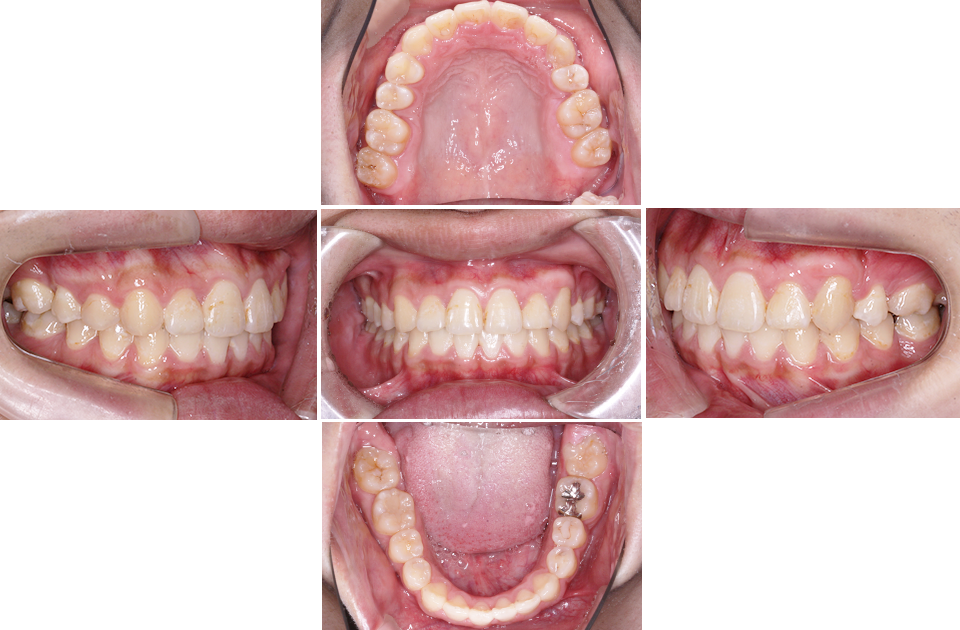

矯正前

矯正後

矯正前 正面

矯正後 正面

矯正前 右側

矯正後 右側

矯正前 左側

矯正後 左側

矯正前 上顎

矯正後 上顎

矯正前 下顎

矯正後 下顎

主訴 凸凹の歯並びを治したい。虫歯が多い。

年齢 10代男性

治療法 上下顎マルチブラケット装置

抜歯の有無 上顎左右第一大臼歯、上顎左側第一小臼歯、下顎左右側第一大臼歯

治療期間 2年5ヶ月